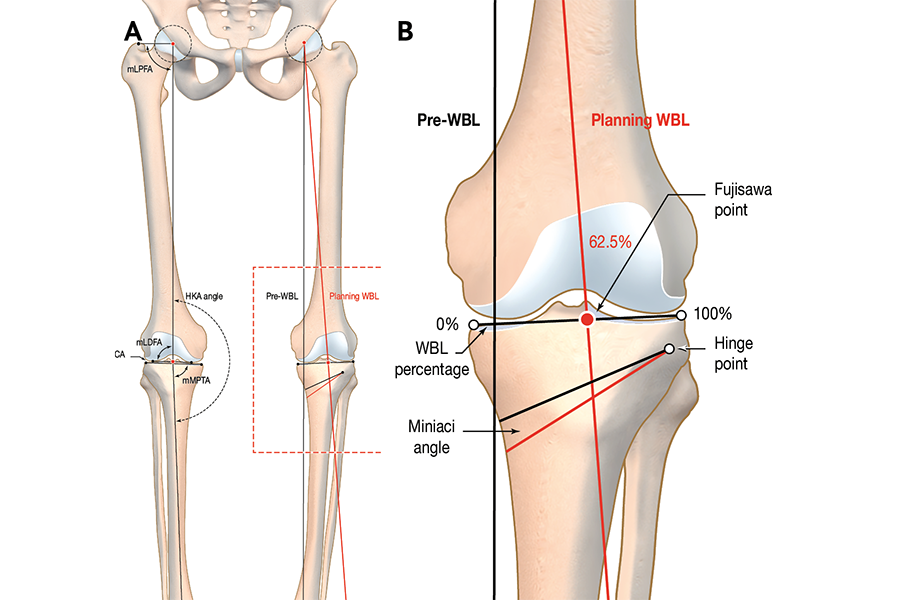

Ostéotomie fémorale distale dans la pathologie dégénérative du genou : indications, planification, techniques et complications

🖂 dejour.secretariat@lyon-ortho-clinic.com , Guillaume Demey Lyon Ortho Clinic - Clinique de la Sauvegarde, 29B avenue des Sources, 69009 Lyon, France